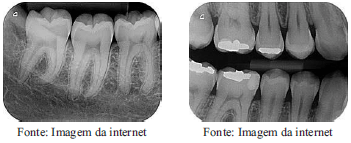

As imagens abaixo ilustram dois tipos de radiografias odontológicas. A denominação CORRETA dessas radiografia é, respectivamente: